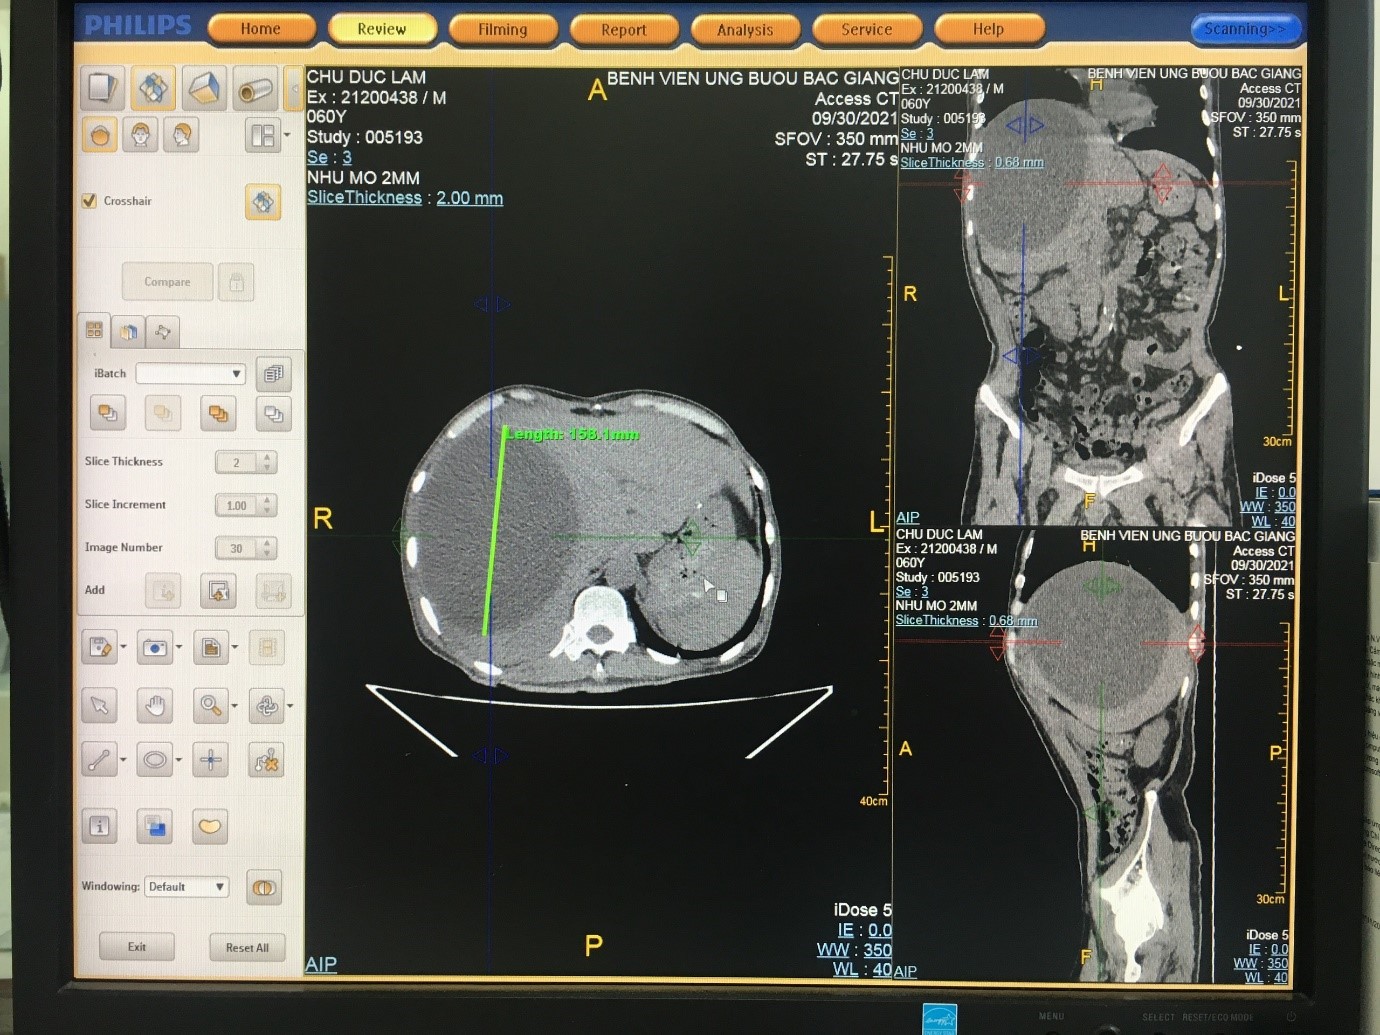

Ngày 30 tháng 9 năm 2021, bệnh nhân Chu Đức Lâm, 60 tuổi, đang điều trị tại khoa Hồi sức cấp cứu, được chẩn đoán có Ổ áp xe lớn tại gan, biểu hiện: đau tức hạ sườn phải và sốt nhẹ, thể trạng gầy yếu, tiền sử Ung thư dạ dày đã phẫu thuật cách đây 2 tháng nên bác sỹ điều trị quyết định can thiệp tối thiểu để hạn chế một cuộc mổ sẽ ảnh hưởng nhiều đến sức khỏe bệnh nhân. Bệnh nhân được chuyển xuống khoa Chẩn đoán hình ảnh và tiến hành chọc hút dẫn lưu dưới hướng dẫn của siêu âm. Bác sỹ Nguyễn Văn Dũng- Trưởng khoa Chẩn đoán hình ảnh và các y bác sỹ trong ê kíp đã trực tiếp tiến hành hút dẫn lưu được hơn 2 lít dịch mủ màu vàng, bơm rửa ổ áp xe, gửi bệnh phẩm nuôi cấy làm kháng sinh đồ. Bệnh nhân đã giảm cảm giác đau tức ngay sau khi được tháo mủ và hoàn toàn tỉnh táo, khỏe mạnh và được chuyển về khoa Hồi sức cấp cứu điều trị tiếp. Khoa Chẩn đoán hình ảnh đã tiến hành dẫn lưu nhiều ca bệnh được chẩn đoán áp xe gan nhưng đây là trường hợp có ổ áp xe lớn nhất trong số các ca bệnh đã thực hiện, thể trạng bệnh nhân yếu và nguy cơ vỡ ổ áp xe vào ổ bụng là rất lớn.